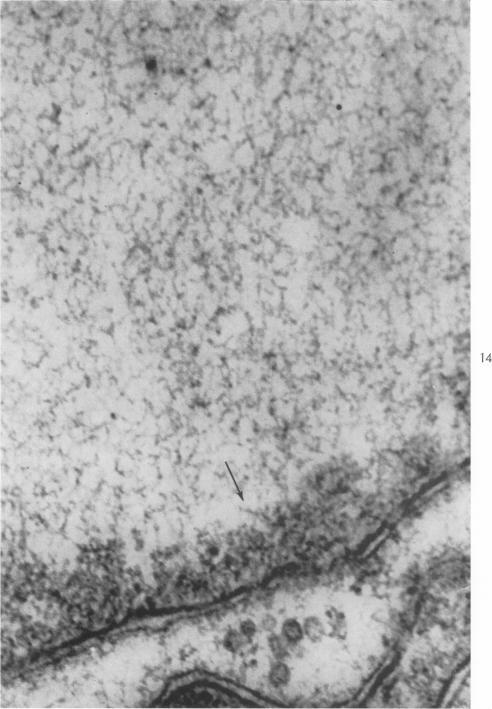

Electron microscopic observations on the development of herpes simplex virus.

J Exp Med. 1959 Oct 1;110(4):643-56. doi: 10.1084/jem.110.4.643.